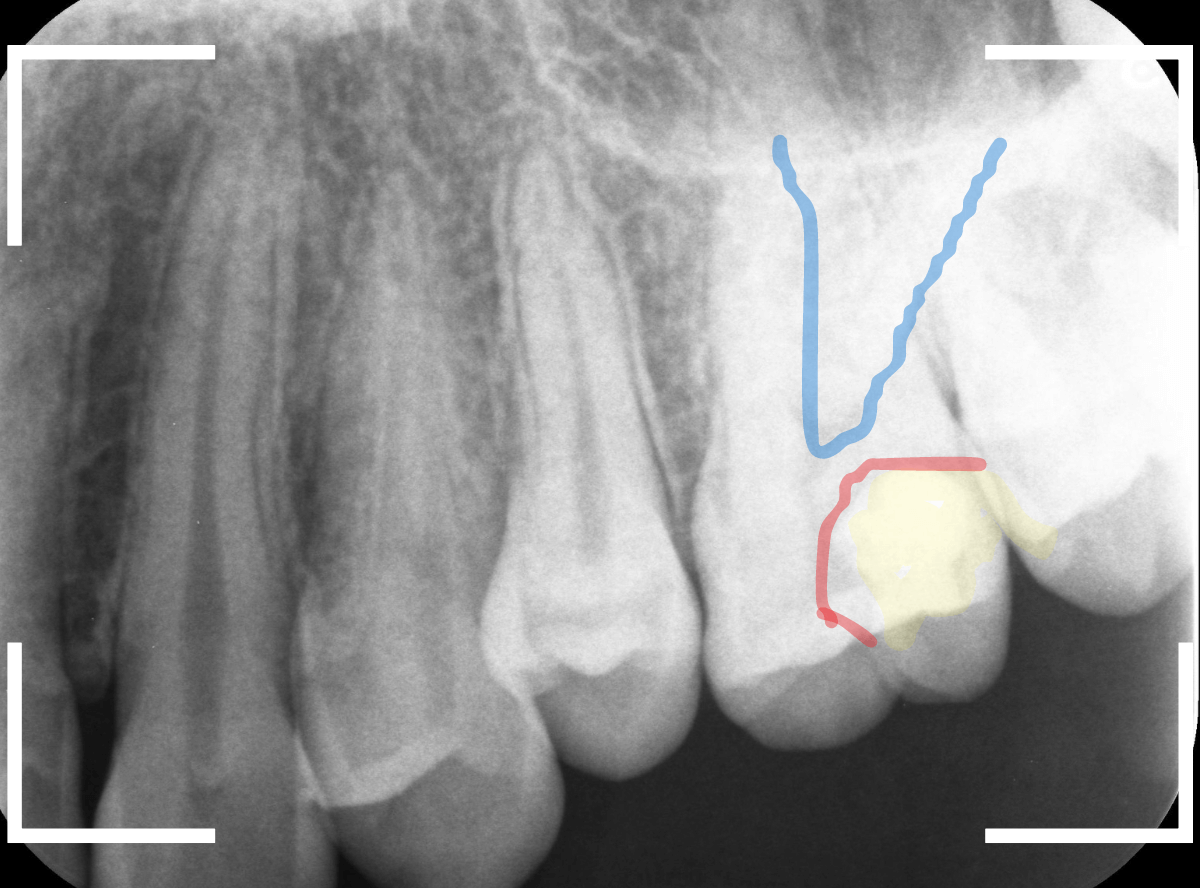

虫歯の治療希望で来院された患者さんです。

レジンが欠けて大きな穴が空いているのが見えます。

このような場合は、中で虫歯が進行している事が多いです。

(レジンの中で虫歯が進行してレジンに穴が空いた、レジンが欠けたのを放置して虫歯が進行したパターンなどがあります)

レントゲン写真で確認します。

青い線が歯の神経です。

赤い線が虫歯と思われる部分です。

思った通り、神経に達してしまいそうな大きな虫歯です。

患者さんには、神経を取る治療が必要な可能性が高い事を説明します。